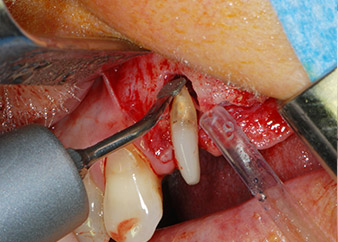

Einen Monat nach dem Eingriff waren sowohl die Schmerzen als auch die Entzündung an Zahn 24 minimal, die Zahnbeweglichkeit lag jedoch noch bei Miller-Klasse 2. Nach Freilegung und Reinigen des infizierten periapikalen und periradikulären Gewebes wurde das Ausmaß des Knochendefizits deutlich (Abb. 2 und 3).

An der bukkalen Wurzel fehlte der gesamte vestibuläre und distale Knochen. Das Attachment beschränkte sich weitgehend auf die palatinale Wurzel, was die anfängliche schlechte Prognose unterstreicht. Auch Zahn 27 wies ein verringertes horizontales Attachment (vgl. Abb. 12) und eine kleine apikale Aufhellung (Abb. 1) auf, allerdings ohne klinische Symptome.

kompletter Verlust von Knochen und Attachment

Abb. 2 und 3: Bei der Freilegung einen Monat nach endodontischer Revision und Beginn einer systematischen Parodontalbehandlung weist die bukkale Wurzel des Zahns 24 einen kompletten Verlust von Knochen und Attachment auf.